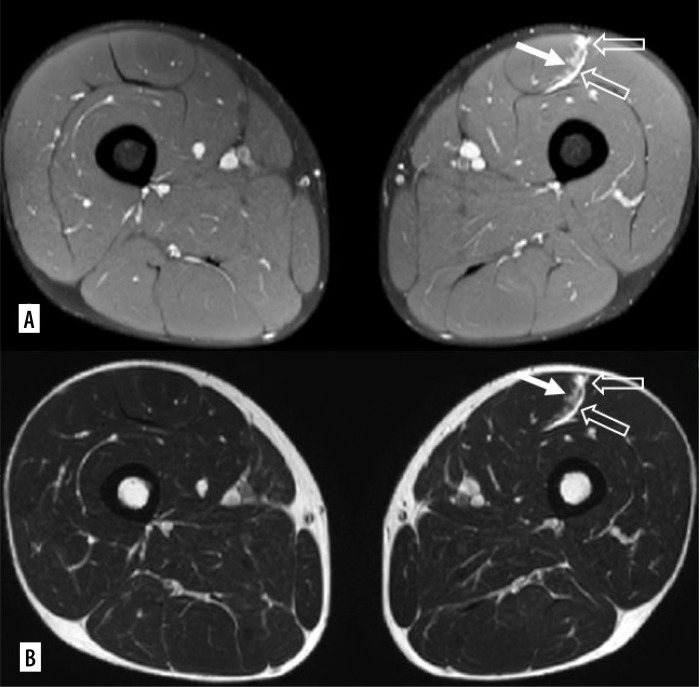

Purpose: Muscle injuries are common in competitive sports. Magnetic resonance imaging (MRI) and ultrasound (US) are the most commonly used methods for evaluating muscle injuries. Several classification systems for muscle injuries have been published. Mueller-Wohlfahrt et al. introduced a new classification system in 2013, currently the most widely used, employing grading to reflect the diverse spectrum of muscle injuries observed in athletes. The differentiation between lesions classified as type 3A (minor partial muscle tear) and 3B (moderate partial muscle tear) remains to be precisely established. In relation to recovery time, we researched possible statistically significant differences.

Material and methods: We conducted a comprehensive analysis of 100 MRI studies that were performed on high-level professional athletes who exhibited clinical signs of lower limb muscle injuries. We selected individuals whose myotendinous or myofascial lesions could be classified as 3A or 3B, based on the Mueller-Wohlfarth (MW) classification. The athletes were then categorised into groups based on the presence or absence of fluid collection at the site of injury. The study's medical practitioner provided data regarding the duration of the injury and the return to sporting activities. Regarding statistical analyses, a linear regression test was conducted to examine the correlation between the variable "fluid collections" and the duration of the injury. Following this, Fisher's t-test or the Mann-Whitney test was applied.

Results: The results of the association between "blood collection" and "duration of injury" revealed a statistically significant correlation. The median value of return to play (RTP) in patients with haemorrhagic collection (median = 29) was significantly higher in comparison with patients without haemorrhagic collection (median = 19), with a difference between the 2 samples of 10 days.

Conclusions: Our study highlights how this distinction could be easily practiced by recognizing the presence of a haemorrhagic collection and how it predominates in determining a worsening of the prognosis and therefore an extension of the RTP. Hence, we can conclude that athletes who do not have blood collection, but only interstitial haemorrhage between fibres can be considered as type 3A, while athletes with interstitial haemorrhage at diagnosis can be considered as type 3B.